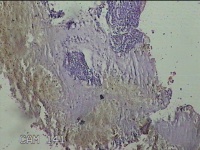

宫内容物

性别

女

年龄

47岁

临床诊断

异常子宫出血

一般病史

阴道流血23天。

标本名称

大体所见

灰白暗红色不规则组织1.7x0.8x0.3cm一块。